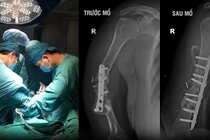

Sau 6 tuần phẫu thuật, kết quả phim chụp X-quang cho thấy can xương hình thành tốt tại vị trí ghép, xương mới được tái tạo mạnh, ổ khớp giả được bù đắp xương mới vững chắc. So với các phương pháp phẫu thuật trước đây, tốc độ và chất lượng liền xương lần này đạt hiệu quả vượt trội hơn.

chan.png

Các bác sĩ đánh giá phim chụp X-quang của trẻ trước và sau phẫu thuật - Ảnh BVCC

Đến tuần thứ 9 sau phẫu thuật, bệnh nhi được tháo bột, bắt đầu tập đi lại. Hiện tại, bé N.L đã có thể đi lại độc lập, tự đến trường, tham gia hoạt động cùng bạn bè như bao trẻ khác.